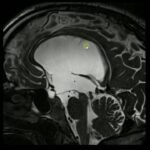

Hidrocefalia é o acúmulo de líquido dentro do cérebro, nas cavidades chamadas ventrículos. Helena precisava de uma cirurgia urgente para tratar a hidrocefalia grave causada pela meningite.